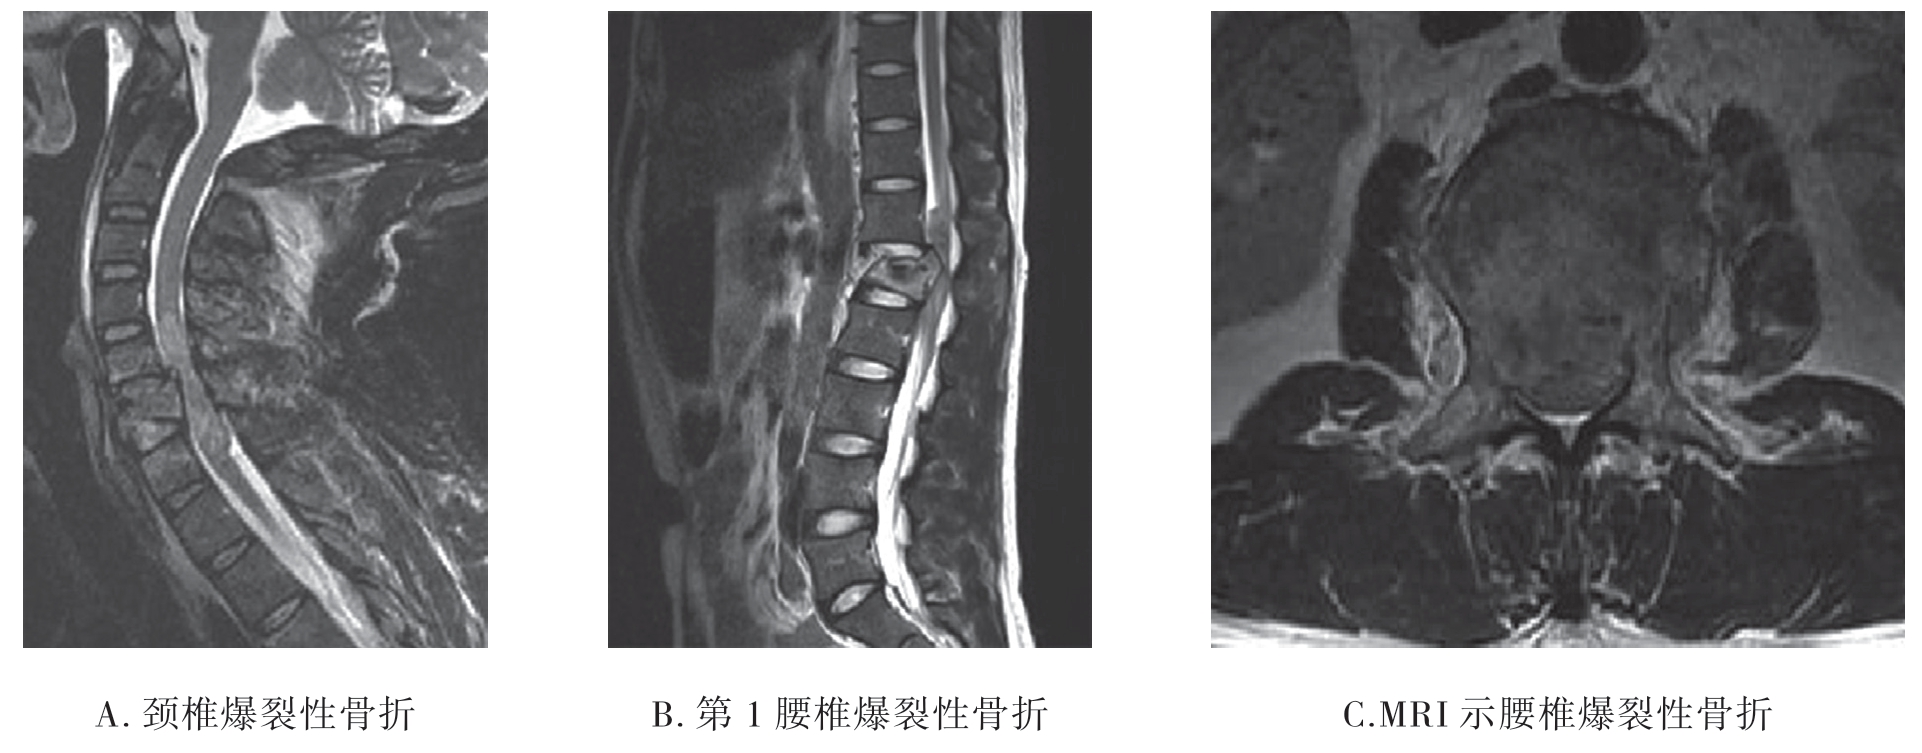

3.MRI检查 MRI能清楚显示脊髓及神经根损伤、韧带、椎间盘及软组织损伤等。损伤的椎体呈粉碎性破裂,椎管断裂、变形;矢状位椎体有不同程度移位,椎间盘破裂并移位,骨折脊椎成角畸形;急性期损伤的脊椎均伴有骨挫裂伤,相邻的脊髓受压变形(图7-2-16)。

图7-2-16 MRI示爆裂性骨折